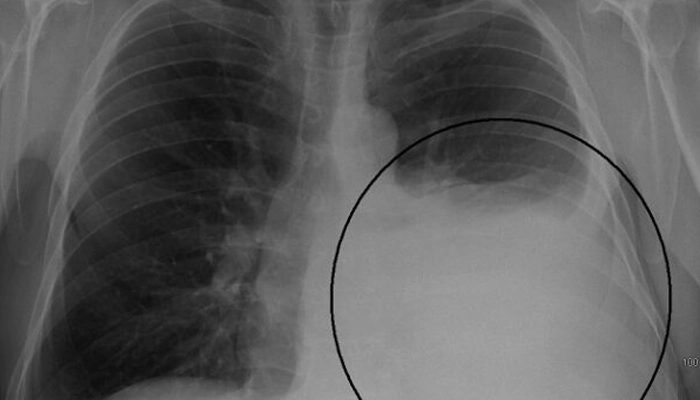

Hình ảnh phổi trắng trên X-quang

Hình ảnh Phổi Trắng cho thấy dịch hoặc mô đặc đã lấp đầy các phế nang hoặc mô kẽ phổi trên diện rộng, làm giảm nghiêm trọng khả năng trao đổi khí.

Hình ảnh "Phổi Trắng" có thể biểu hiện dưới nhiều dạng, giúp định hướng chẩn đoán ban đầu:

| Mẫu Hình Ảnh | Mô Tả | Bệnh Lý Điển Hình |

| Đông Đặc Phân Thùy | Vùng mờ đục đậm đặc, giới hạn rõ theo ranh giới thùy phổi. | Viêm phổi do vi khuẩn (phế cầu). |

| Mờ Đục Lan Tỏa (Khuếch tán) | Các vùng trắng nhỏ li ti hoặc lan rộng khắp cả hai phổi (Bilateral White Lung). | Hội chứng Suy Hô Hấp Cấp (ARDS), Phù phổi cấp. |

| Mờ Mạng Lưới/Khuếch Tán | Hình ảnh các đường trắng (mô kẽ bị dày lên) tạo thành mạng lưới hoặc hình tổ ong. | Xơ hóa phổi, Viêm phổi mô kẽ. |

| Trắng Tuyến Tính | Một bên phổi hoàn toàn trắng. | Tràn dịch màng phổi lượng lớn, Xẹp phổi toàn bộ. |

Hiện tượng phổi trắng xảy ra khi không khí trong phổi bị giảm hoặc mất đi, được thay thế bởi dịch, máu, mủ, tế bào viêm hoặc mô xơ.